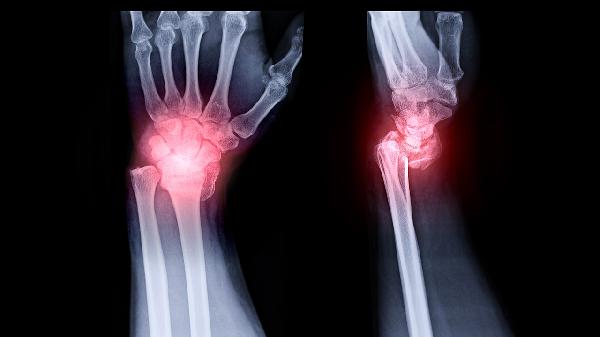

骨囊肿主要表现为局部疼痛、病理性骨折和骨骼畸形三大症状。骨囊肿的症状主要有局部隐痛或钝痛、轻微外力导致的骨折、骨骼膨大或变形。

2、病理性骨折:

骨囊肿导致骨质强度下降,在轻微外力作用下即可发生病理性骨折。骨折部位可能出现异常活动、剧烈疼痛和功能障碍。儿童患者常见于上肢长骨,成人多发生在承重骨。